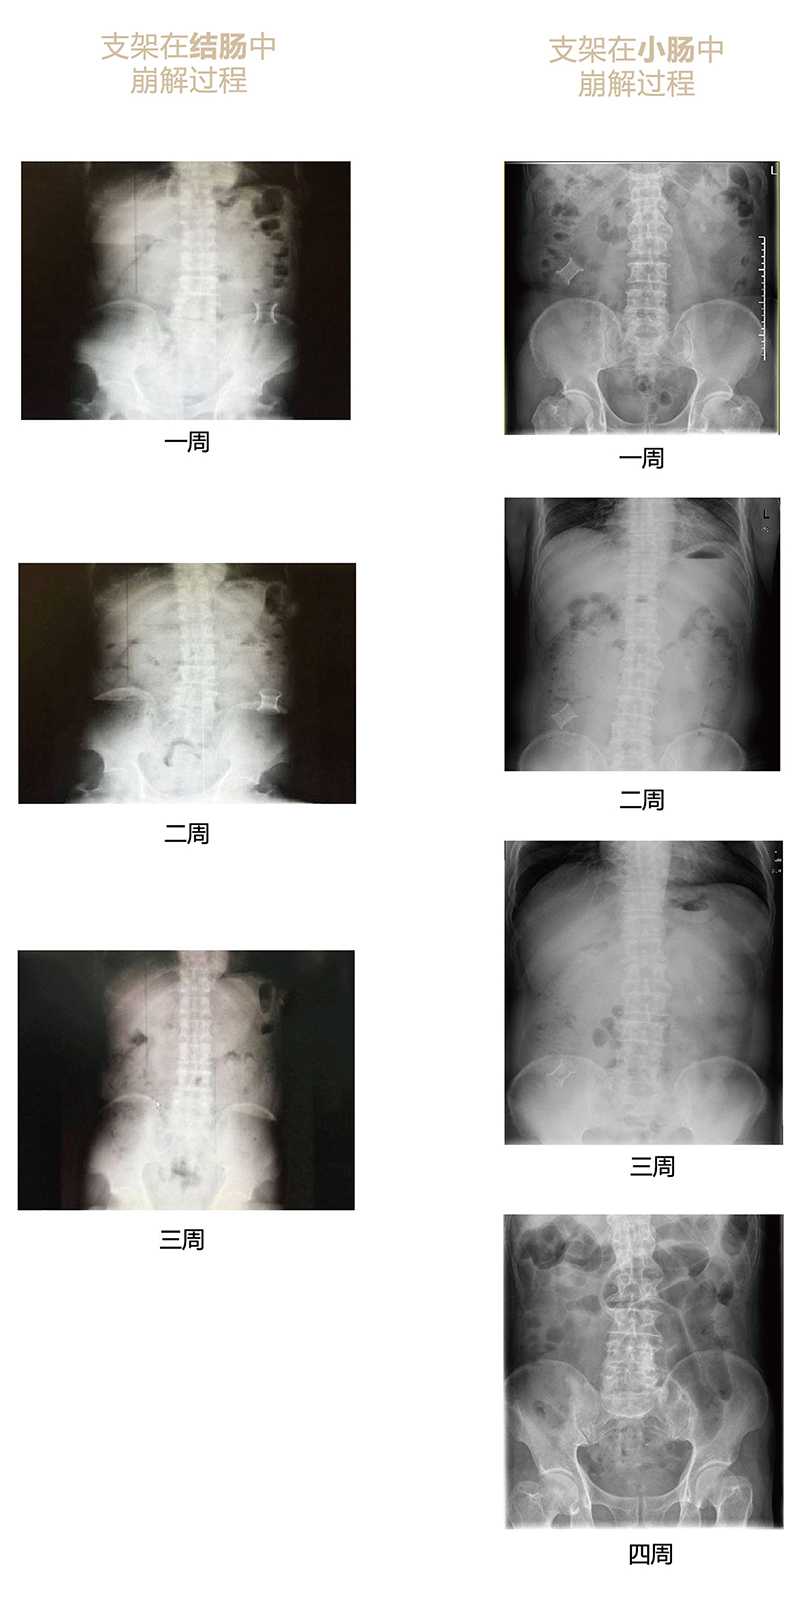

“可崩解腸道吻合器”由聚乙醇酸(PGA)與硫酸鋇按重量比7:1混合注塑制成,在X線下顯影,可動態(tài)追蹤可崩解腸道吻合器(支架)在腸道內(nèi)崩解過程。

為解決該問題,蔡秀軍教授在“支架法空腔臟器吻合技術(shù)”的理念基礎(chǔ)上,又發(fā)明了“蔡氏腸轉(zhuǎn)流術(shù)”,這是一種應用“可崩解腸道吻合器HB型(可崩解腸轉(zhuǎn)流支架)”(發(fā)明專利號:201910794214.3),的支架法腸道轉(zhuǎn)流術(shù),此創(chuàng)新術(shù)式既能保護低位吻合口,更避免了回納術(shù)。可崩解腸轉(zhuǎn)流支架在直腸癌根治術(shù)中植入遠端回腸,可確保完全阻斷腸腔,用腸造瘺管在轉(zhuǎn)流支架近端行腸造瘺,起到完全轉(zhuǎn)流的作用。腸轉(zhuǎn)流支架在二至三周內(nèi)逐漸崩解,并在四周內(nèi)完全排出體外,恢復腸道通暢后拔除造瘺管,避免了傳統(tǒng)造口回納的二次手術(shù)。該創(chuàng)新術(shù)式具有方法簡單、吻合時間短、人體內(nèi)無異物永久殘留、不破壞吻合口粘膜下血管,并能預防吻合口漏、可避免人工肛門留置及二次手術(shù)、治療周期可縮短至二至四周、患者生理心理創(chuàng)傷顯著減少。